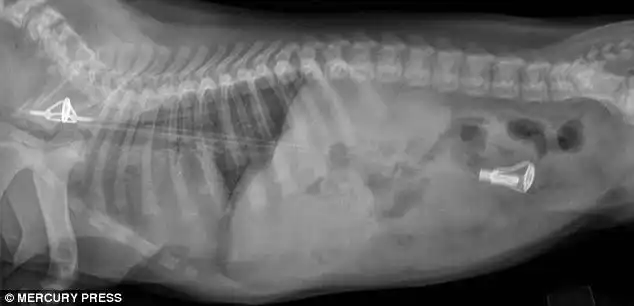

Лабрадор, проглотивший 3 массивных рыболовных грузила

Три 200-граммовых грузила извлеченные из его желудка